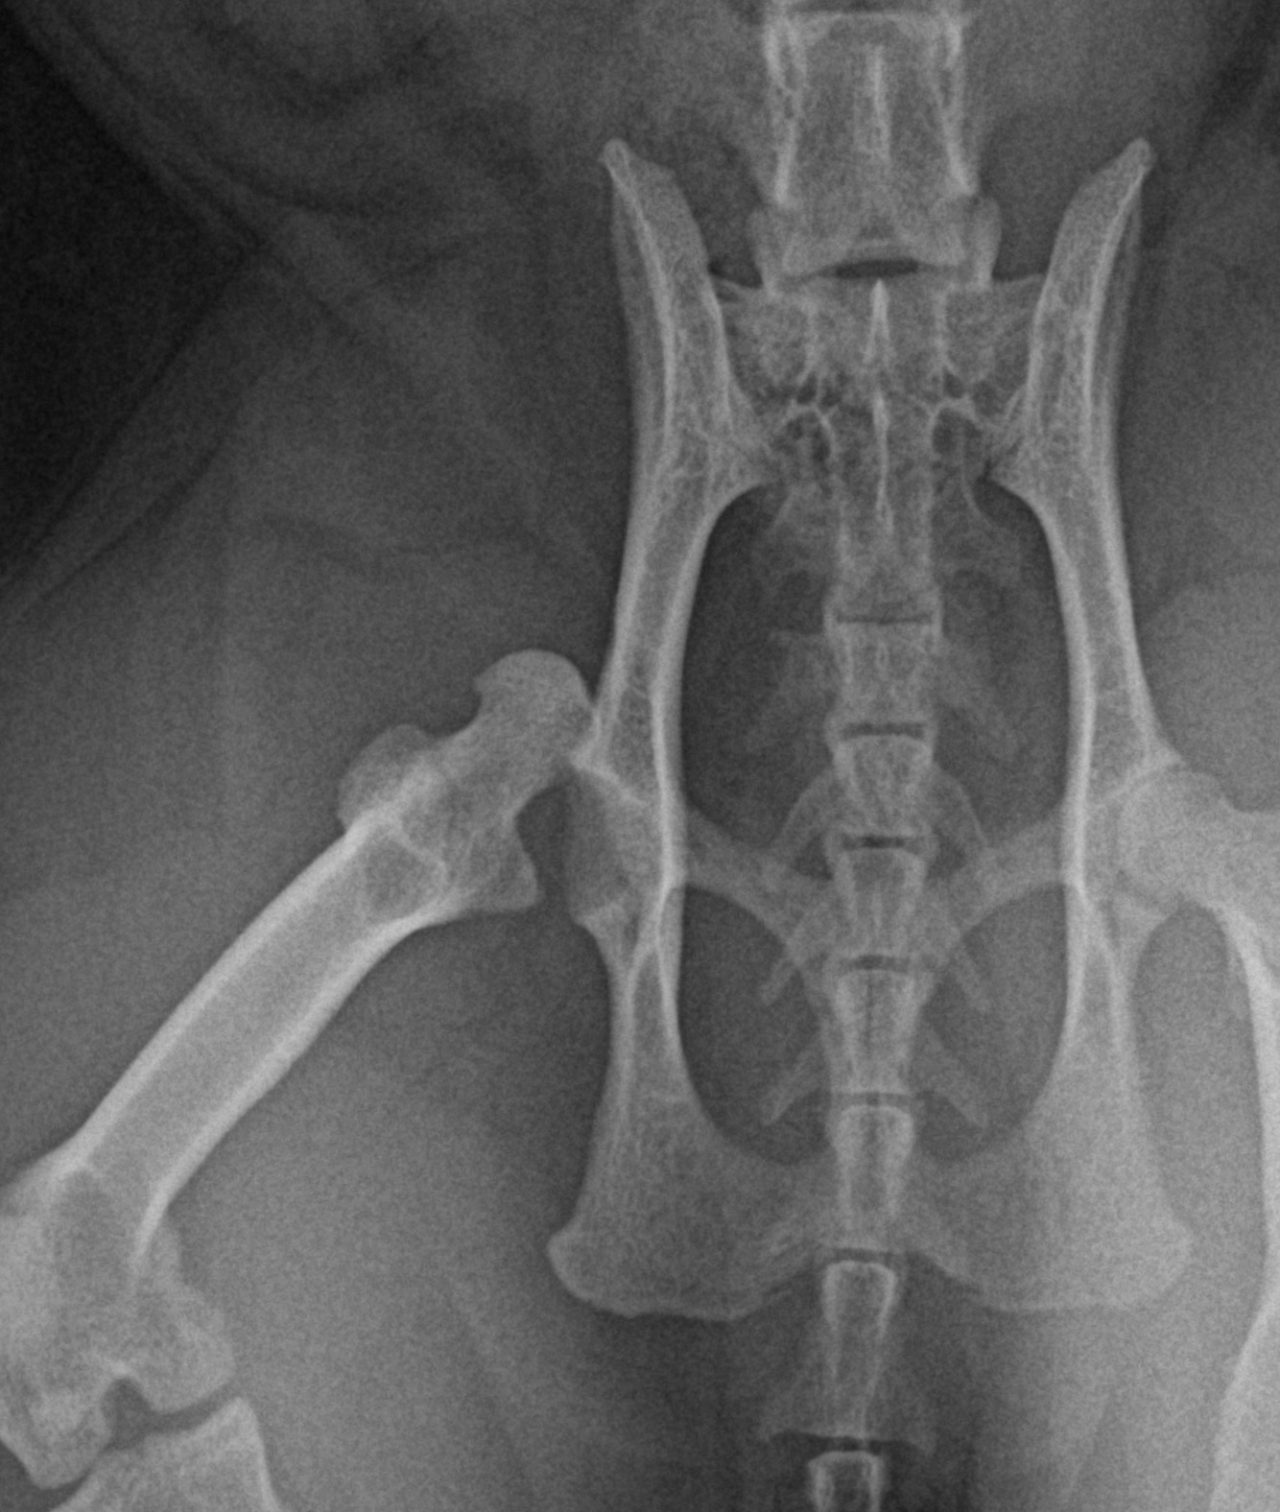

猫の股関節脱臼 外出から帰宅すると猫ちゃんが右後肢を跛行しているとのことで、救急で来院されました。エックス線では右股関節の背側前方脱臼が確認されました。トグルピンと人工靱帯により脱臼した大腿骨を寛骨内に整復します。しばらく安静が必要となります。 症例カテゴリー 放射線治療整形外科軟部組織外科脳神経外科内科腫瘍外科救急・集中治療リハビリテーション科腫瘍内科内視鏡科脳神経科呼吸器外科中医・漢方猫の腎移植循環器科